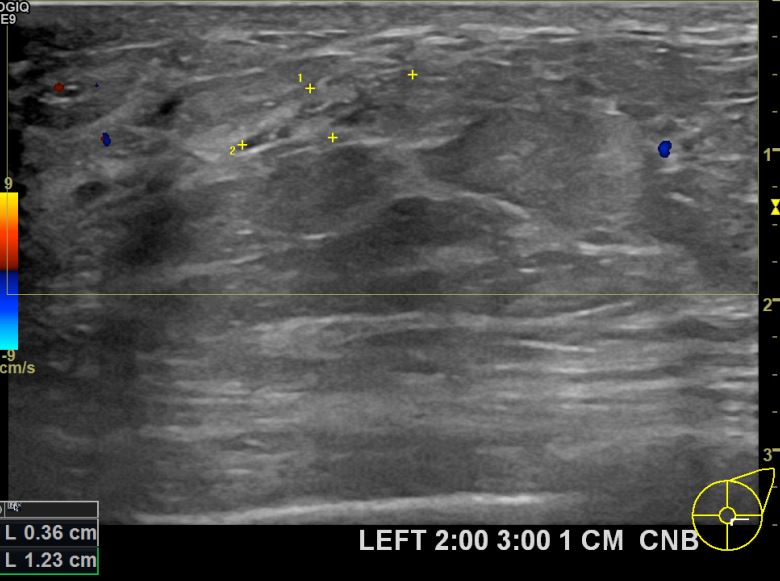

상기환자 외부건진상 이상소견으로 조직검사권유받고 내원하신 40대 여성분으로 좌측유방멍울  조직검사시행후 유방암 진단되었습니다